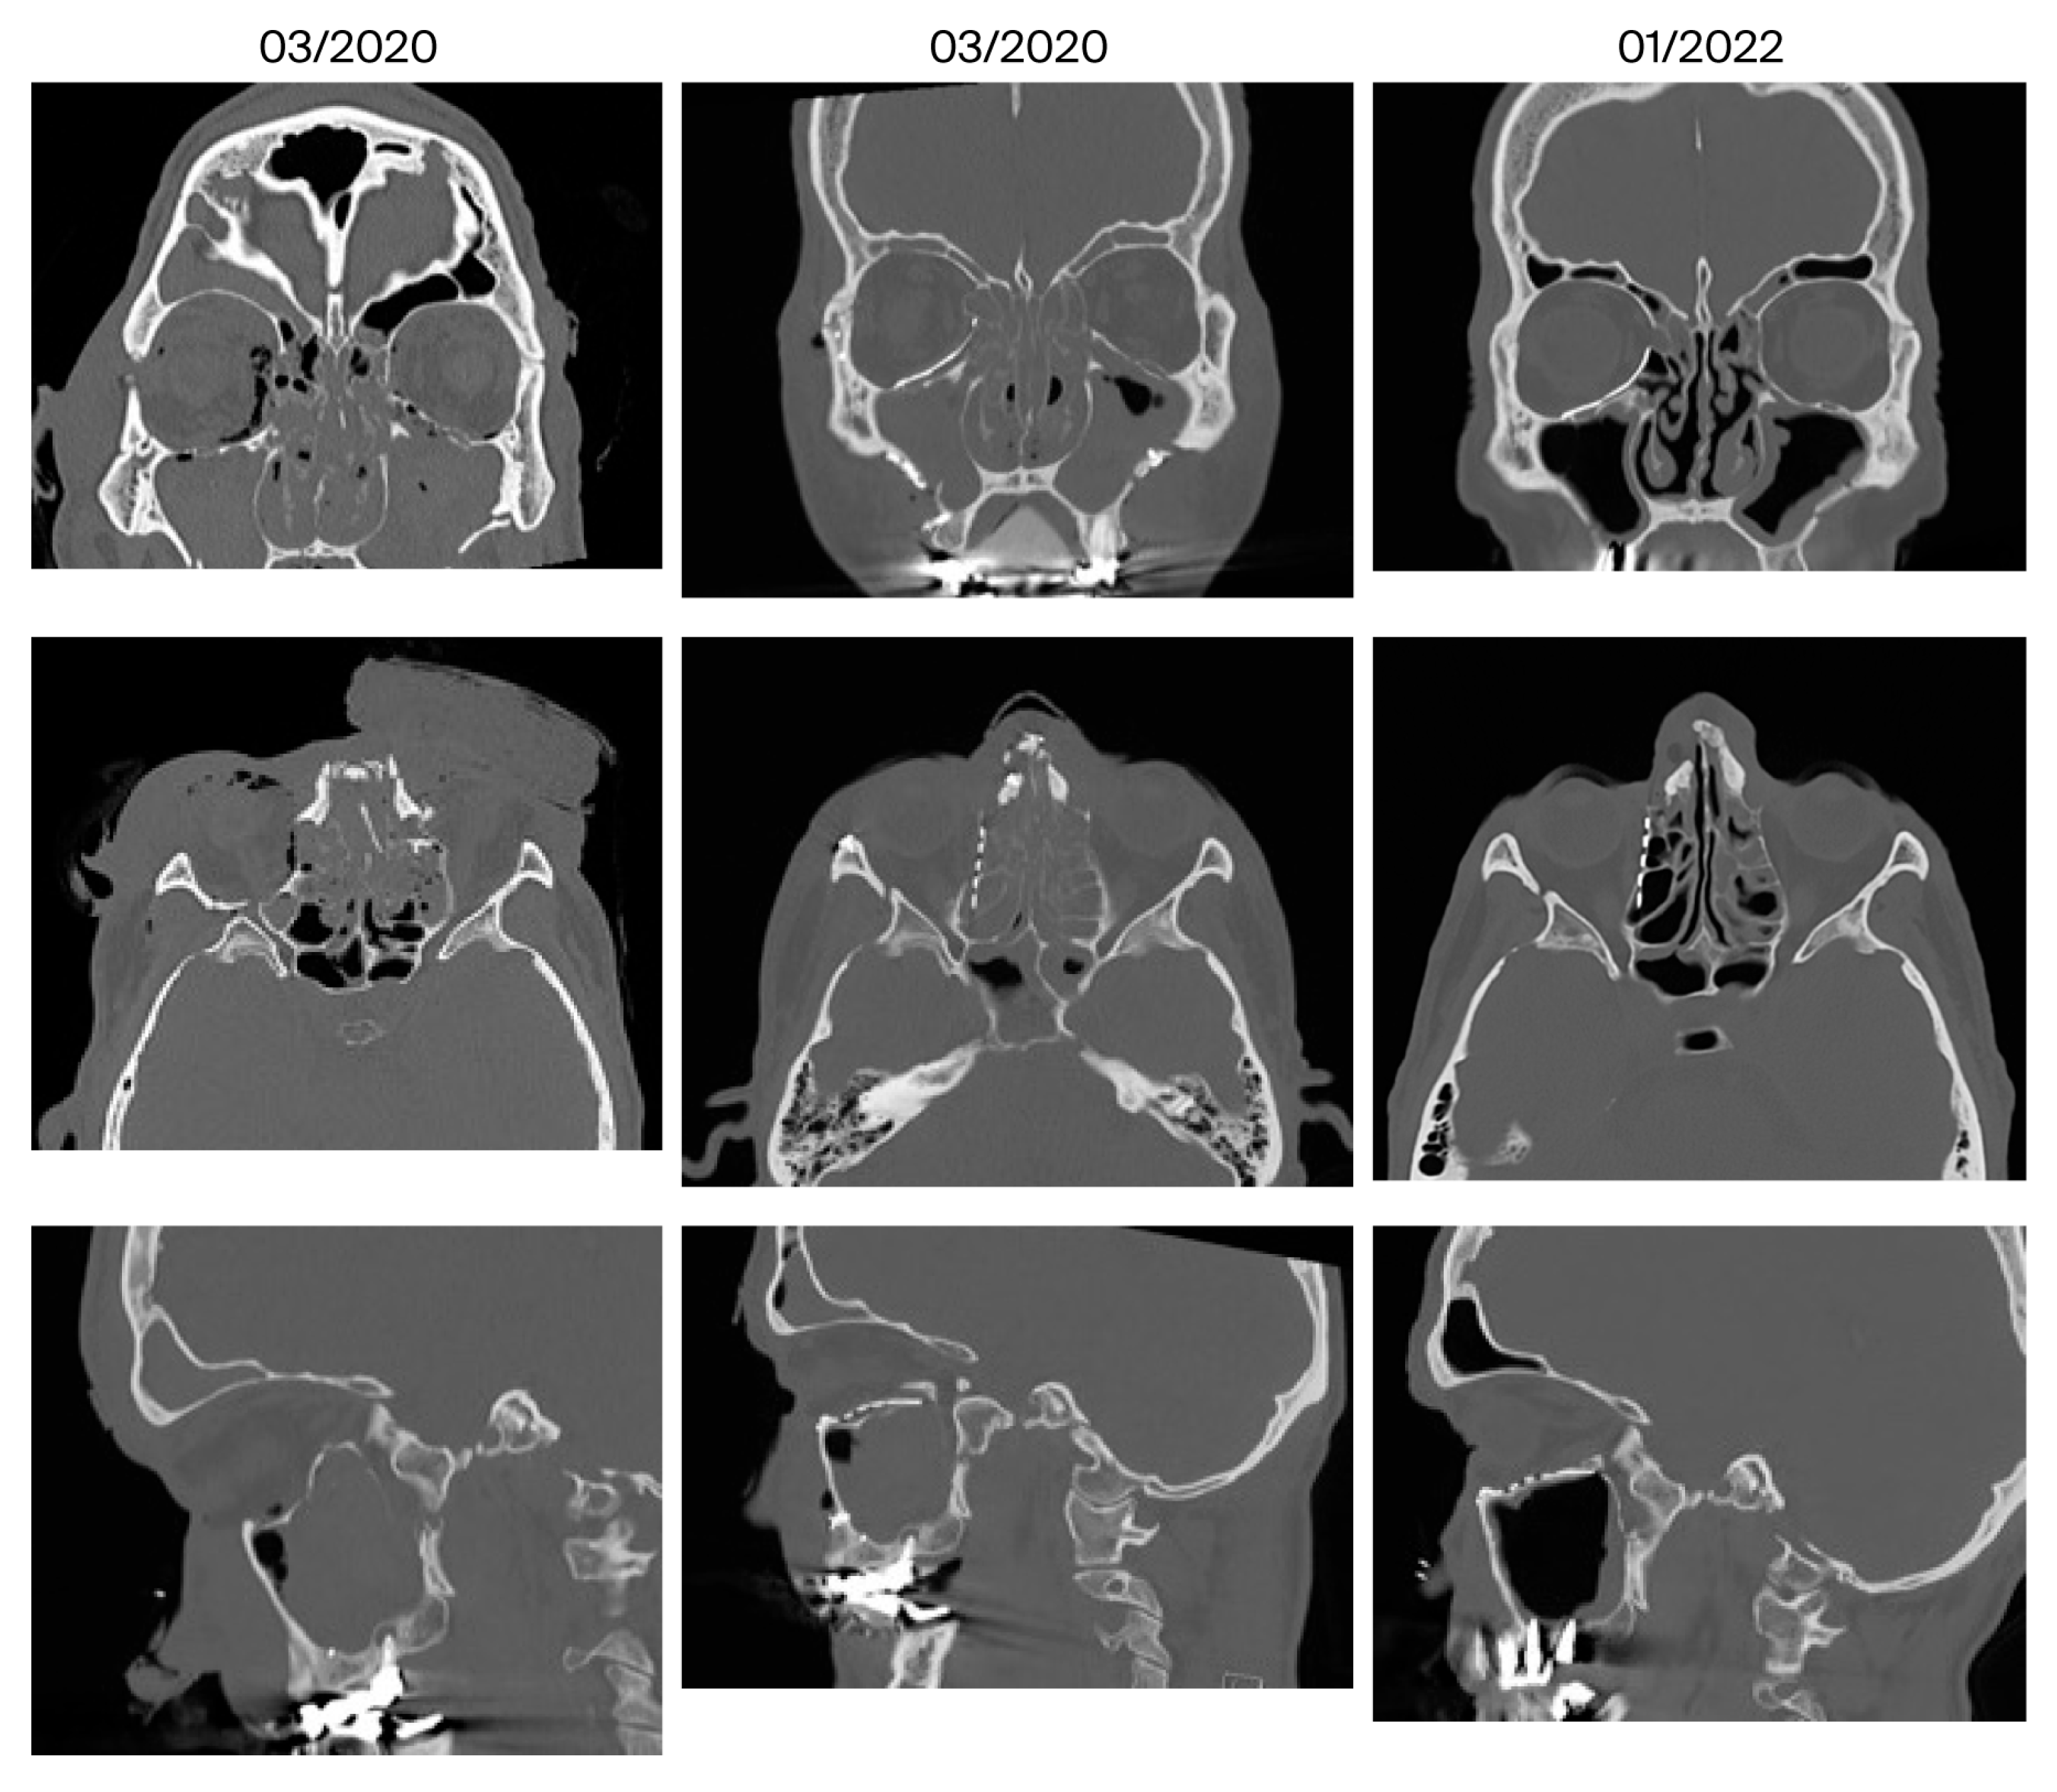

| 10 | March 2020 January 2022 (22 months) | Anosmia, migraine | Mucosal swelling | 3/5 | No | Ethmoidal | Yes |